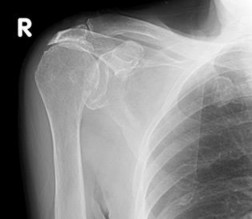

a. Chụp X-quang thường quy47,48

Bao gồm chụp X-quang khớp vai tư thế trước sau, và X-Quang khớp vai nghiêng kiểu Lamy

Dựa trên phim tư thế trước sau ta có thể xác định hình dạng củ lớn xương cánh tay, KC chỏm xương cánh tay và bề mặt dưới của MCV. Việc thu hẹp KC chỉ ra sự di chuyển lên trên của đầu xương cánh tay, điều đó đã được liên kết với rách của gân CX, đặc biệt là cơ trên gai.

Hình 1.20. X-quang khớp vai tư thế trước sau trong rách lớn CX thấy chỏm xương cánh tay ở sát ngay mặt dưới xương MCV.

Nguồn: Theo nguồn AAOS (American Academy of Orthopaedic Surgeons)